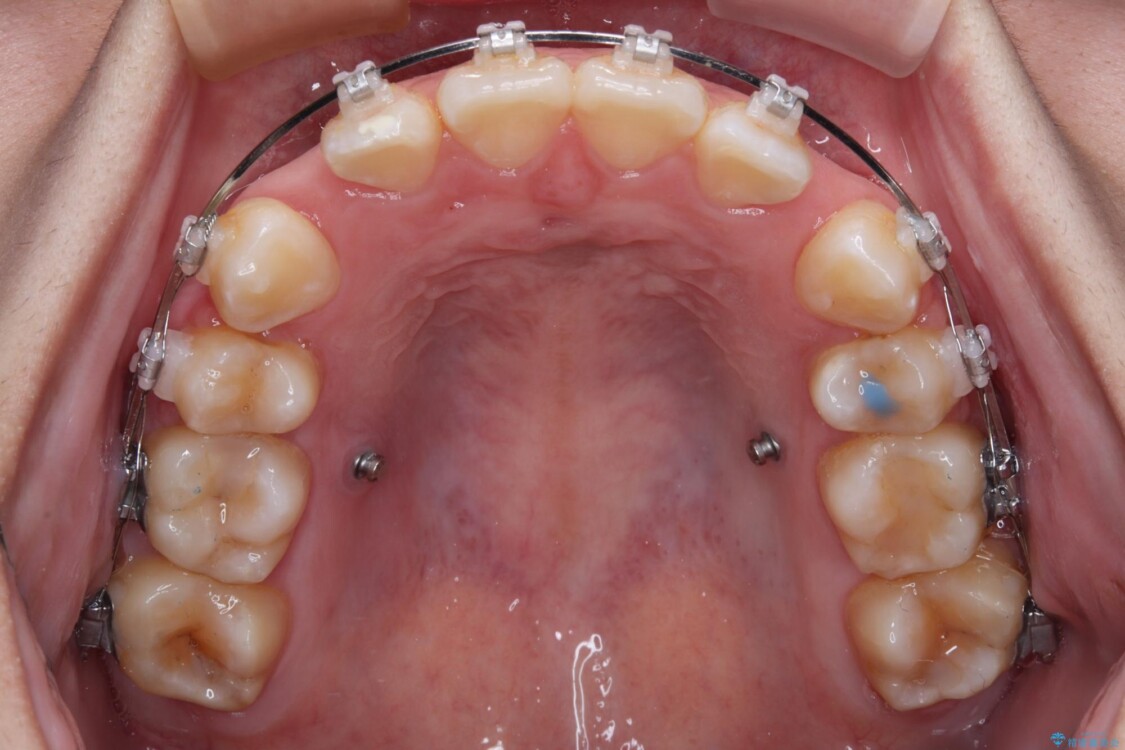

治療途中

• 転勤でも安心して治療継続 抜歯スペース閉鎖と深い噛み合わせ改善のワイヤー矯正 治療途中画像